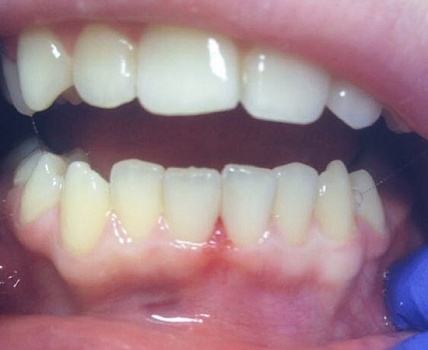

Изменения тканей, которые окружают корни зубов, к сожалению, неизбежны и с возрастом наблюдаются у всех, однако в разном объеме. Так, на развитие пародонтита влияет болезнетворная микрофлора полости рта, которая есть у каждого из нас, но на мы в силах повлиять на ее количество.